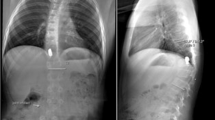

Barros, T., Zigler, J., Aito, S. et al. Gunshot wound to the spine. Spinal Cord 39, 541–544 (2001). https://doi.org/10.1038/sj.sc.3101186